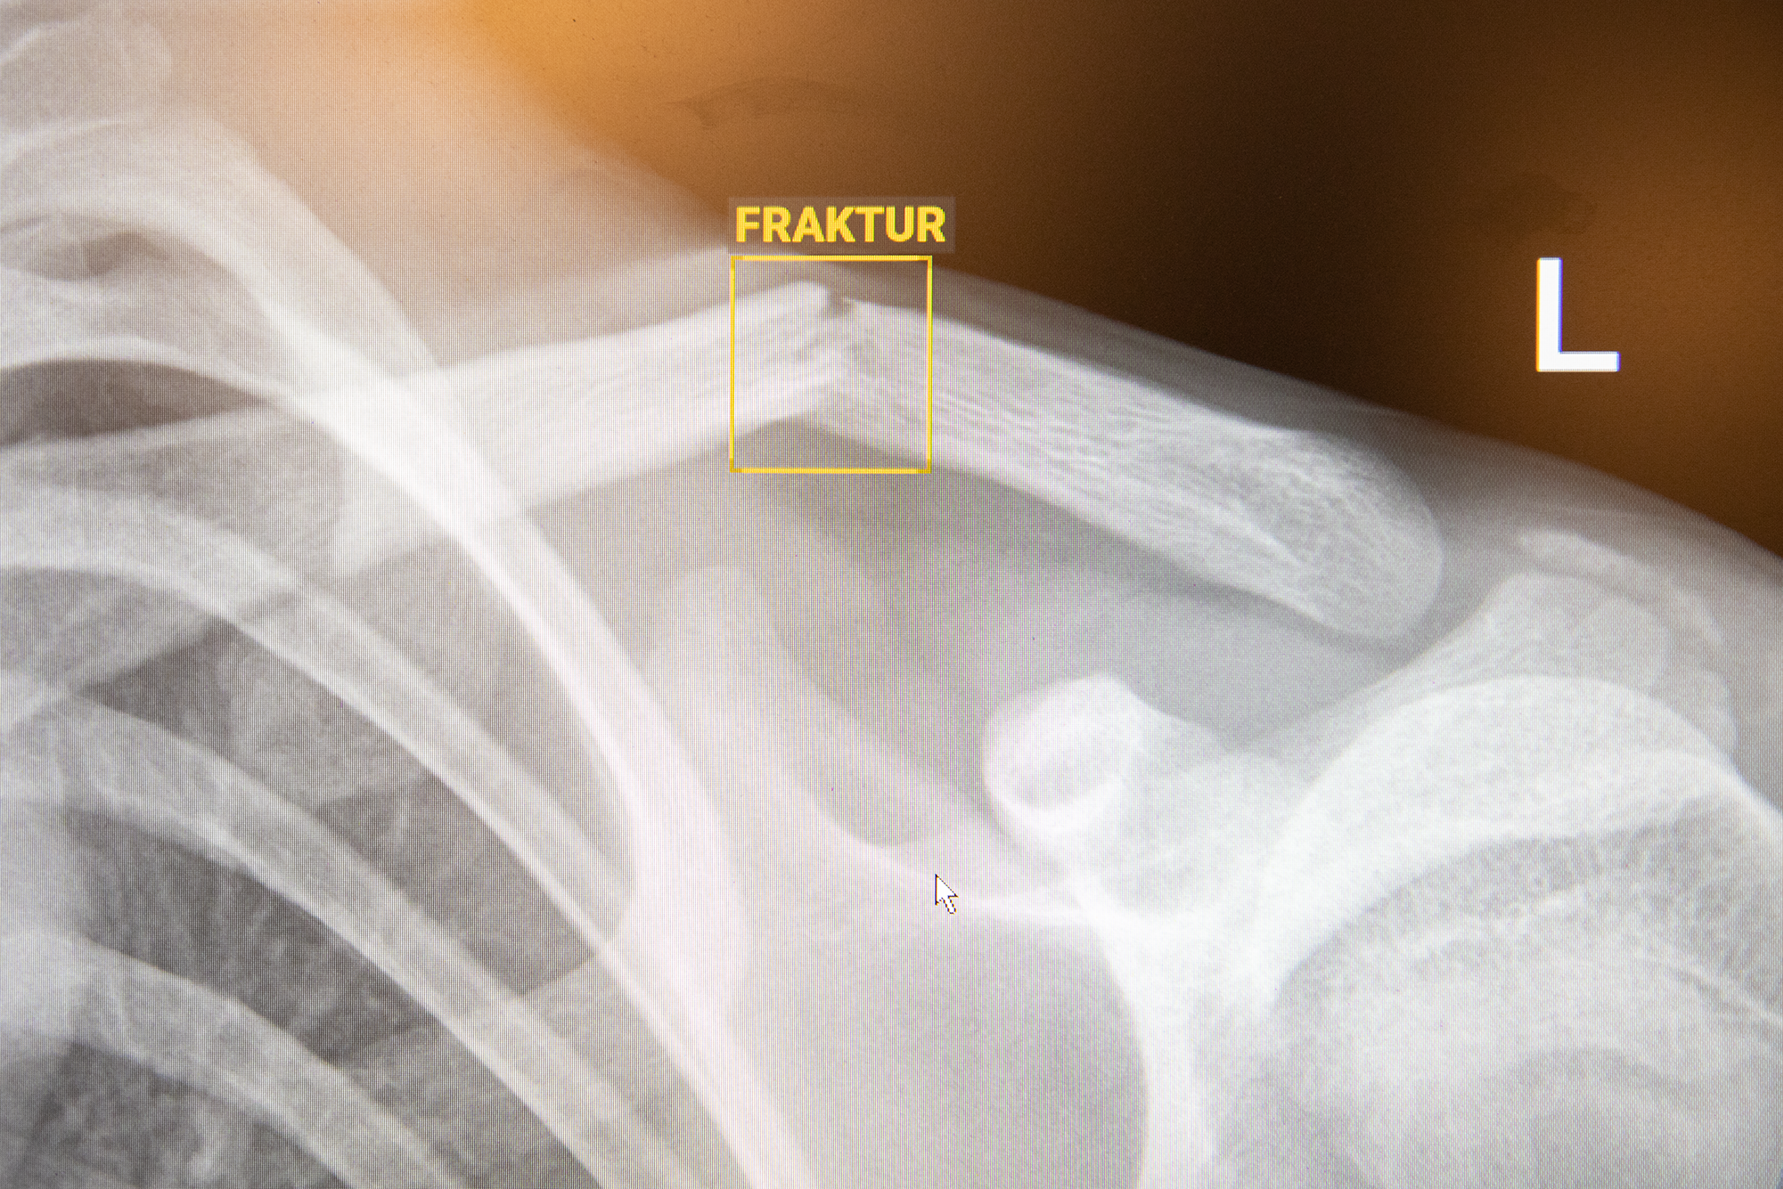

Nå er klinikken i gang med kunstig intelligens (KI) for å diagnostisere brudd, som tredje i rekken på Ahus etter Ski og Kongsvinger. KI-algoritmen BoneView fungerer som en støtte for radiologene når de tolker røntgenbildene. Den største effekten får pasientene, legevaktene og ortopedene.

På maks to minutter markerer algoritmen om det er brudd eller ikke. Den er svært treffsikker, men svaret blir alltid kontrollert av en spesialist i ettertid - uavhengig av om pasientene blir sendt hjem eller ikke.

- KI-algoritmen finner bruddskader på røntgenbilder, og fungerer som en beslutningsstøtte for radiologene.

- Verktøyet heter BoneView, og er levert av Gleamer. Applikasjonen er trent til å oppdage skader som brudd, bein som er ute av ledd og væske i ledd. Den kan brukes på barn ned til to år.